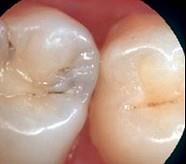

龋好发于牙齿的 ( )

A.滞留区B.舌面C.牙尖D.自洁区E.边缘嵴

A

解析